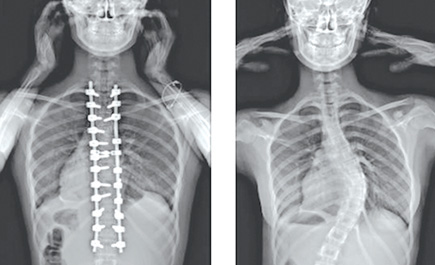

العيوب الخلقية للعمود الفقري والانحناءات الشديدة يمكن علاجها

- عند وجود الجنف فإنه يتم عرض الطفل على استشاري العمود الفقري الذي يقوم بعمل الأشعات السينية اللازمة وقياس درجة التقوس ونسبة الزيادة فيه.. وبصفة عامة فإنه لا يوجد حتى اليوم دواء يعالج الجنف او يمنع ظهوره، ولكن أغلب الحالات التي يتم اكتشافها مبكراً في الأطفال تكون درجتها بسيطة وتحتاج فقط لمتابعة دورية. أما إذا حصلت زيادة في درجة التقوس فمن الممكن استخدام حزام طبي في محاولة لإبطاء التقوس.. وفي الحالات التي يكون التشخيص فيها متأخراً فإن التدخل الجراحي يكون ضرورياً ويتم بنجاح تام مع استخدام التقنيات المتطورة في العلاج ووجود الطبيب المتخصص في علاج هذه الحالات.

حالات العيوب الخلْقية يُمكن علاجها

* هناك تشوهات خلْقية تصيب العمود الفقري منذ الولادة، ما هي الإمكانية لعلاجها؟

- يعتمد التشخيص على الفحص السريري الدقيق إضافة للفحص الشعاعي لتحديد ما إذا كانت هناك إصابة للعظم. كما تفيد أشعة الرنين في فحص الحبل الشوكي والأعصاب والغضاريف لتبيّن سلامتهم من الأمراض.. ويُعد تشخيص هذه الحالات في البداية مهم جداً لوضع خطة علاجية مبكرة لتلافي حصول أية مضاعفات.